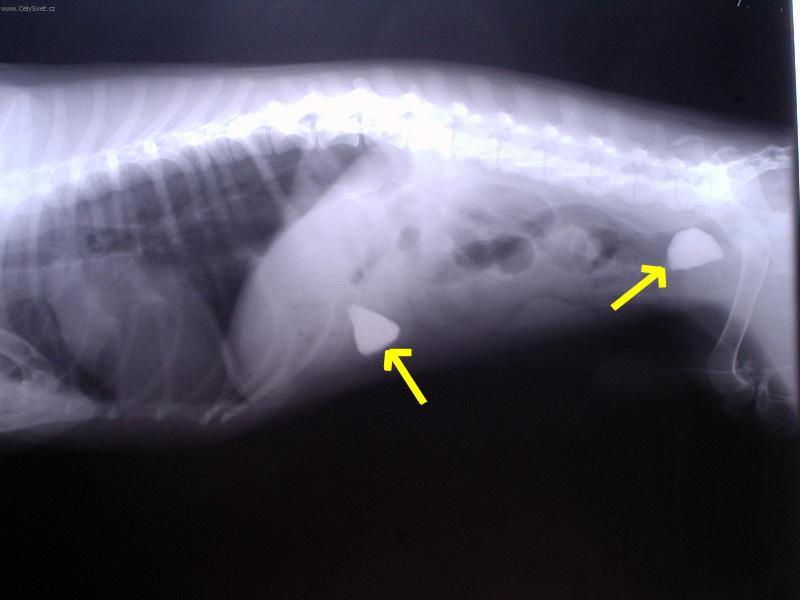

Foto galerie (fotky, obrazky): Cizí tělesa v zažívacím traktu a kostní trus.

Clanek: Cizí tělesa v zažívacím traktu a kostní trus.